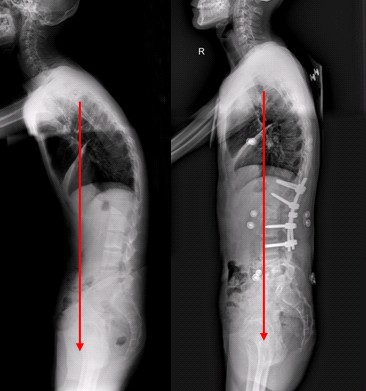

强直性脊柱炎会驼背?为什么

强直性脊柱炎为什么会引起脊